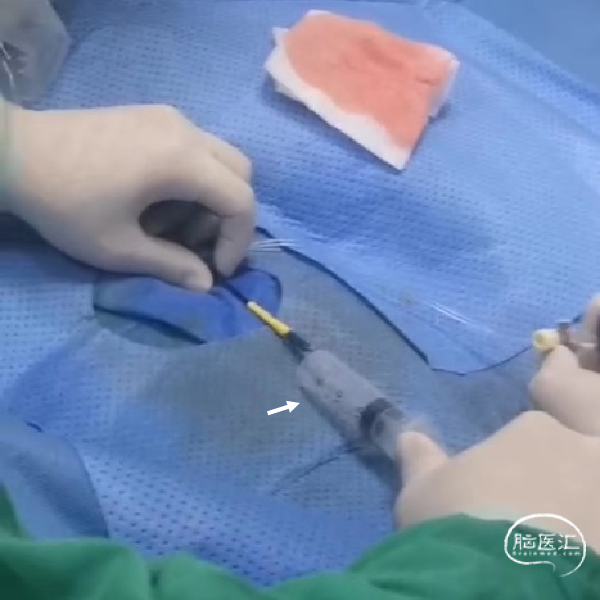

不减影图像中长鞘(白色箭头)和抽吸导管(红色箭头)位

持续接触抽吸90秒后,回撤抽吸导管;抽吸导管进入长鞘之前,开启长鞘负压抽吸;发现血栓卡在长鞘头端、抽吸导管撤出长鞘后发现长鞘内无回血(白色短箭头)。20ml注射器连接长鞘、持续负压抽吸下撤出长鞘;长鞘在进入8F穿刺鞘前,开启穿刺鞘负压抽吸(白色长箭头)。最终成功将血栓从长鞘内抽吸出。